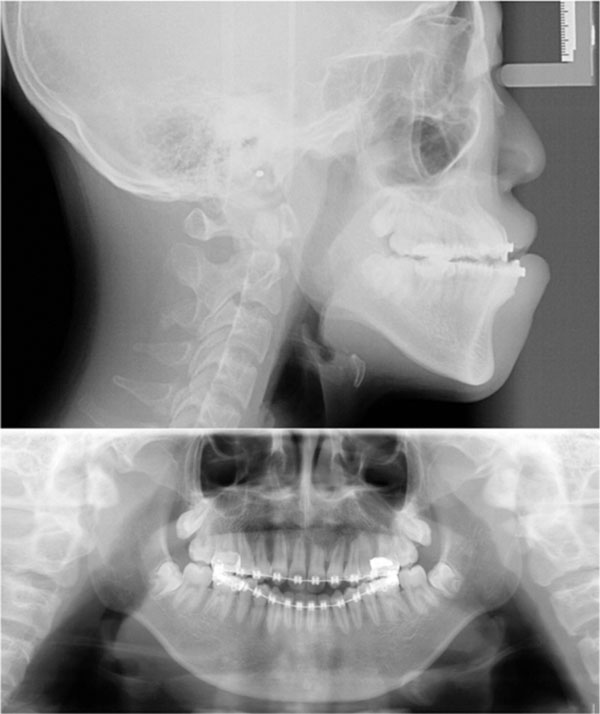

Presurgical radiograph.

After extraction of all the supernumerary and lower deciduous teeth, the 0.022Х0.028 in slot straight-wire fixed appliance was used to level maxillary and mandible teeth. Once the upper teeth were aligned (for 6 months with 0.012, 0.014 and 0.016 NITI wire) and space recovered for the impacted central incisors by means of the nitinol spring (for 6 months with 0.5 mm stainless steal wire), surgery assisted traction for central incisor was performed individually. In brief, the labial surface of the maxillary central incisor was surgically exposed. An attachment was then bonded to the teeth surface and the flap fully sutured back to the former position. The twisted stainless steel ligature wire (0.2 mm) that has been previously placed in the attachment was then drawn occlusally with the main archwire of 0.5 mm stainless steel wire. Ten months later, both central incisors erupted into the oral cavity, the brackets were banded and proper guidance was provided to the central incisors during normal eruption. In order to create space for the impacted upper canines and premolars, bilateral upper lateral incisors with severe root resorption and retained primary teeth were extracted. Then, surgery assisted eruption guidence for impacted canines and premolars were performed individually. The main archwire of 0.5 mm stainless steel wire with loop was placed, the power chain was connected between impacted canine and the loop. Four months later, the canine was guided into the upper arch (Fig. 2). After 10 months of alignment of all the dentition (with 0.016, 0.016x0.022, 0.017x0.025, 0.018x0.025NITI wire), .018x.025 stainless steel wire was placed. In this stage, all the impacted teeth were guided to normal position, the patient and parents were satisfied with the teeth but disliked the concave face (Fig. 3). Hence, the patient was suggested to receive surgery. The bimaxillary orthognathic approach including Lefort I osteotomy. Bilateral sagittal split ramus osteotomy (BSSRO) and genioplasty was performed to correct skeletal problem. Titanium screws were used for rigid fixation. Maxillomandibular fixation with an occlusal splint was performed for 4 weeks. The MEAW technology (0.018x0.025 stainless steel wire) together with vertical elastic and short class III elastic was performed to establish the ideal occlusal relationship. After 8 months of post-surgical orthodontic treatment, Ideal occlusion was achieved and the fixed appliance was removed. Clear retainers were worn in both jaws. The retainers were maintained all day for 6 months, subsequently, were worn only during the night for another 1 year. Total active treatment period lasted for 5 years including 1 year missing for operation fee preparation.